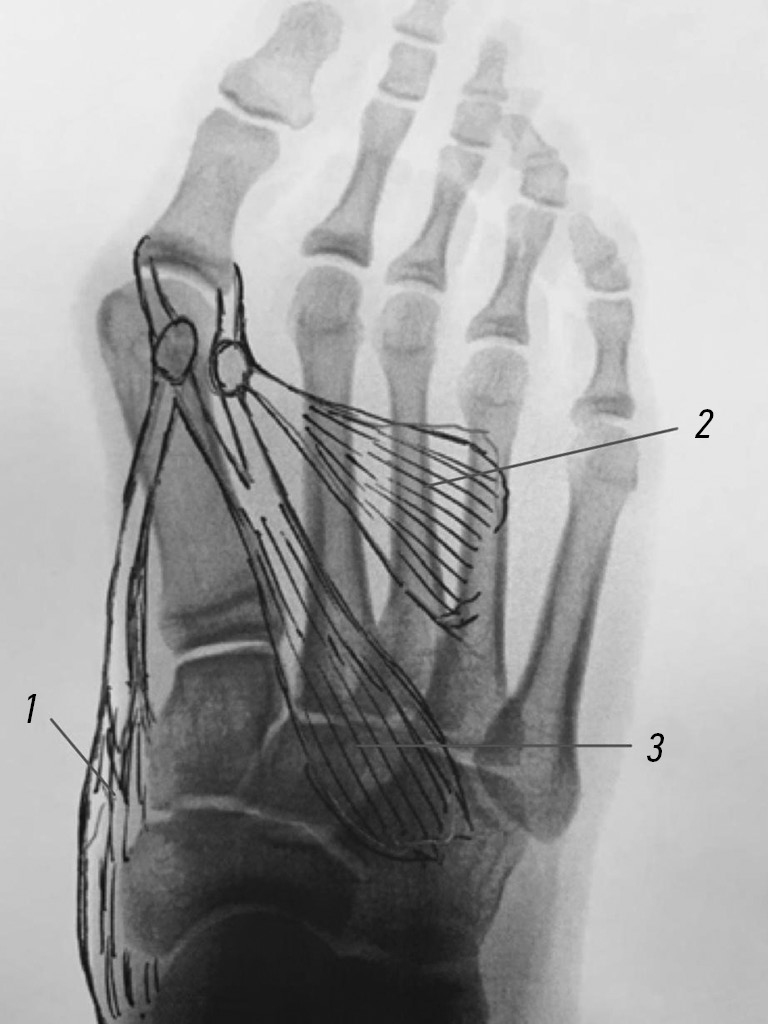

With hallux valgus, the muscle balance is disturbed, which, from our point of view, is the main cause of the development and progression of hallux valgus deformity of the big toe. Owing to the imbalance between the traction of the musculus abductor hallucis and the musculus adductor hallucis, the sesamoid bones are laterally displaced with the plantar–lateral displacement of the abductor, which starts to function as a flexor of the big toe (Fig. 7). In this case, the flexion complex, reinforced by the “former” abductor, stretches like a bowstring, causing a gradual varus deviation of the first metatarsal bone and a pollex valgus of the big toe.

Fig. 7. Scheme of the influence of muscles (1, musculus abductor hallucis; 2, musculus abductor hallucis; 3, short flexor of the big toe) on the hallux valgus and varus deviation of the first metatarsal bone, accompanied by lateral displacement of the sesamoid bones, with an external plantar displacement of the musculus abductor hallucis tendon